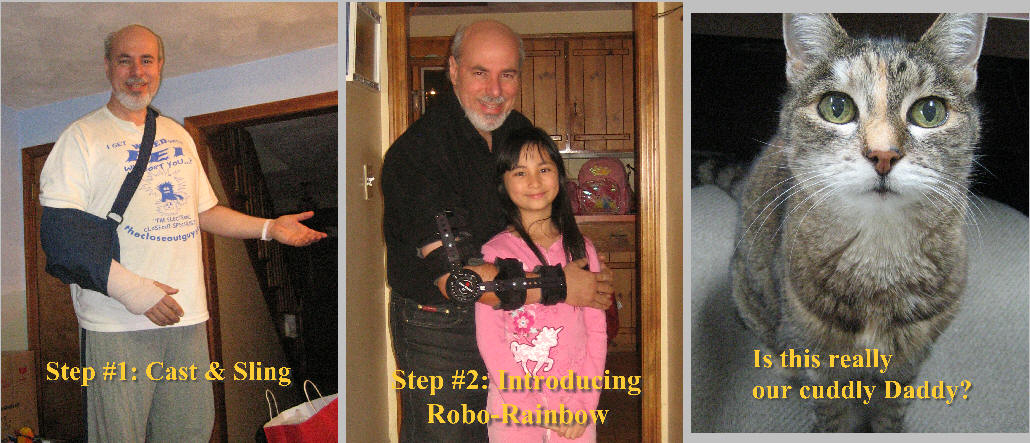

Post op splint limits range. Each week, a "cast technician" dials a larger degree of freedom.

But in my case, it was not set properly. I had almost full freedom of extension from the start!